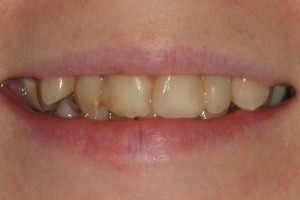

Młoda pacjentka zgłosiła się do naszego gabinetu celem wykonania kompleksowego leczenia zachowawczo-ortodontycznego. Oprócz problemów natury ortodontycznej stwierdzono złą higienę jamy ustnej oraz liczne potrzeby leczenia zachowawczo-endodontycznego. Po wnikliwej analizie telerentgenowskiej oraz analizie modeli zadecydowano o ekstrakcji 2 zębów w łuku dolnym (kła po stronie lewej oraz pierwszego przedtrzonowca po stronie prawej). Plan leczenia obejmował ponadto zamknięcie łuku po brakujących zębach w łuku górnym. Leczenie aktywne trwało 2 lata i 8 miesięcy. W czasie jego trwania pacjentka była regularnie poddawana zabiegom higieny profesjonalnej celem eliminacji zapaleń przyzębia brzeżnego. Po leczeniu aktywnym zastosowano leczenie retencyjne w postaci retainera stałego w żuchwie oraz szyny retencyjnej w łuku górnym.